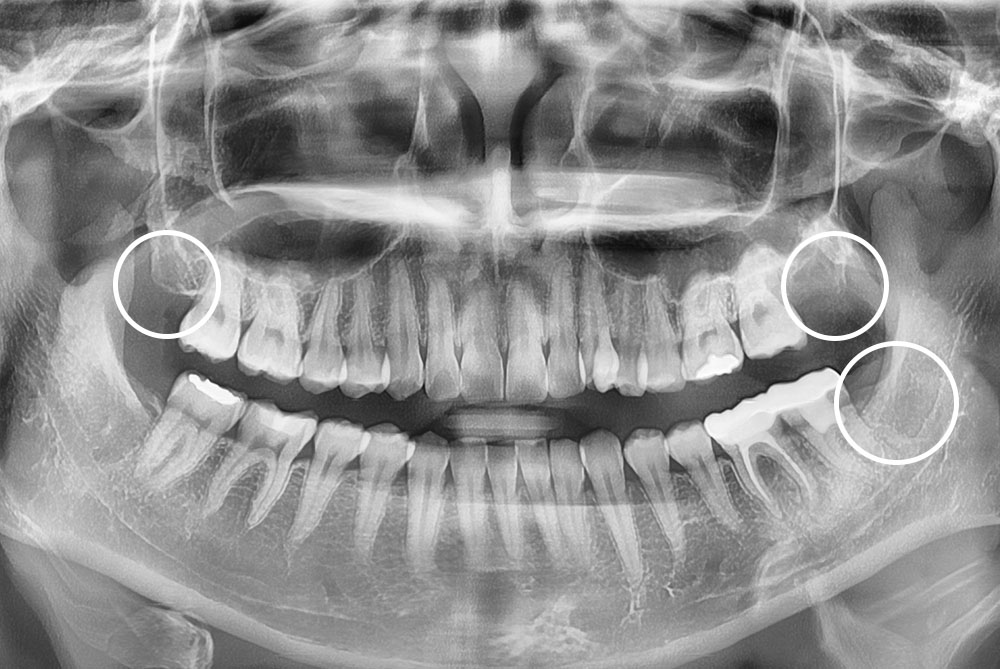

[사랑니] 매복 사랑니 발치

치료전 : 2019-08-13